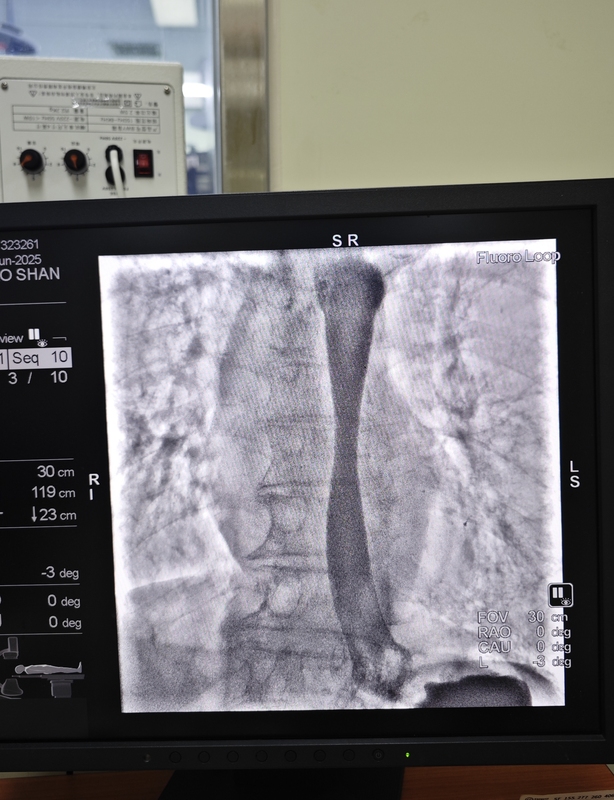

食管癌是一種嚴重的消化道惡性腫瘤,食管癌的主要類型包括鱗狀細胞癌(最常見)和腺癌(較少見)?;颊咭蚴彻馨┦彻塥M窄無法正常進食進水,在DSA引導下食管支架置入術(shù)是一種有效的微創(chuàng)治療選擇,能夠立即緩解由晚期惡性腫瘤引起上消化道梗阻癥狀。食管內(nèi)支架置入,可以解除食管梗阻和狹窄,減輕癥狀,恢復正常吞咽功能,可以讓患者無法正常進食水后有效改善患者營養(yǎng)狀態(tài)、提高其生活質(zhì)量的安全有效方法。對于中晚期食管癌,出現(xiàn)了食道梗阻且無法外科手術(shù)切除,食管支架置入是首選的治療方法,可以立即緩解患者的進食梗阻問題。今天這個患者經(jīng)濟條件有限,孫主任給單獨定制的一枚加長食管支架(大家可以猜猜有多長)。